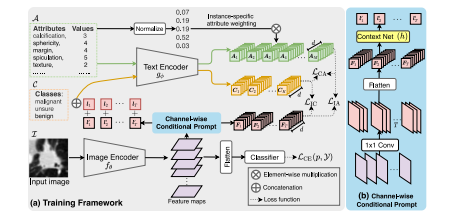

Fig. 12. Context optimization for lung nodule classification.Source: From Lei et al. (2023c)

图12:肺结节分类的上下文优化。来源: 出自雷等人(2023c)的研究